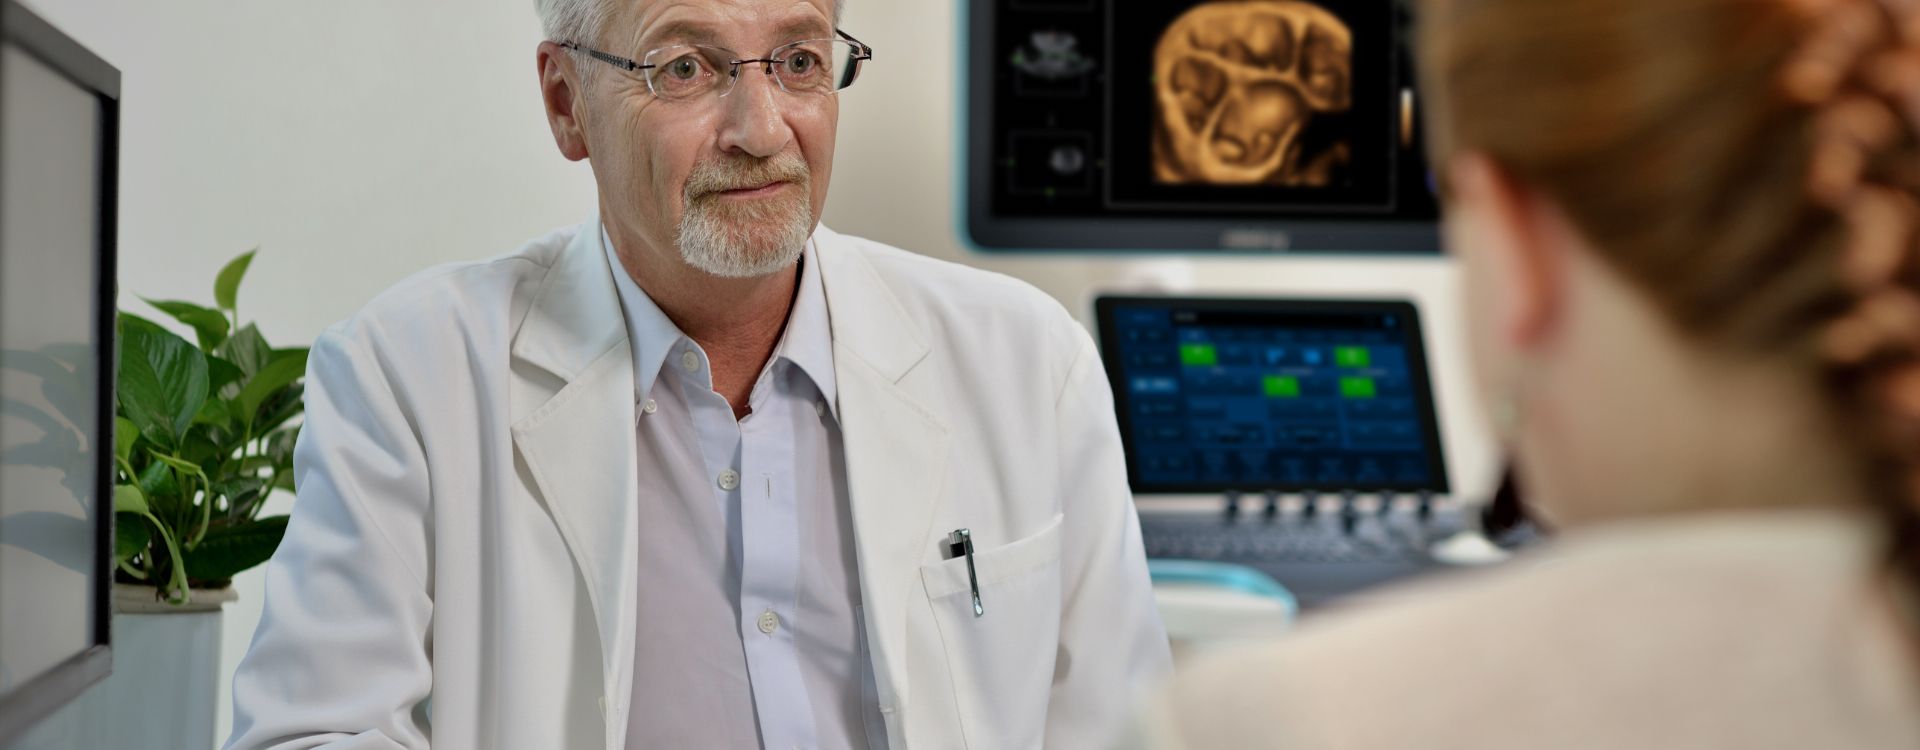

A precis?o fortalece sua confian?a

Imagem geral

As solu??es de imagem geral Mindray Resona ajudam mĂŠdicos a obter resultados mais precisos e eficientes de diagnĂłstico e tratamento por meio de sondas de aplica??o de subdivis?es abrangentes e ferramentas eficientes de aplica??o clĂnica.

Produtos para imagem geral